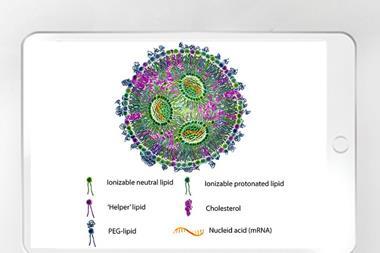

Recent authorisation of Inlexzo ™ (gemcitabine intravesical system) by the US Food and Drug Administration (FDA) offers certain patients with Bacillus Calmette-Guérin (BCG)-unresponsive non-muscle invasive bladder cancer (NMIBC) a novel treatment alternative.

Inlexzo (previously known as TAR-200), remains in the bladder for three weeks per treatment cycle for up to 14 cycles.

Clinical data demonstrating the drug’s high response rate supported the FDA’s decision. In the SunRISe-1 Phase IIb study, 82 percent of patients attained complete response without the need for reinduction, according to Johnson & Johnson. Of these patients, 51 percent sustained this response for at least 12 months.

This data for the company's drug delivery system adds to positive findings presented at the European Society for Medical Oncology (ESMO) Congress in 2023.